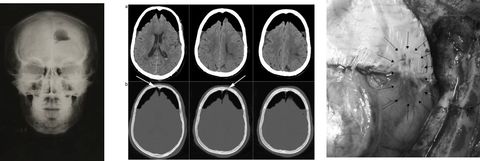

NEUMOENCÉFALO

ENFERMEDAD DE PAGET

NEUROCISTICERCOSIS

MENINGIOMA